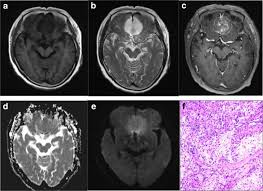

Series 001 — Frontal Lobe Mass (Likely Meningioma) Overview

Initial scan set with key anatomical landmarks and first-pass observations.